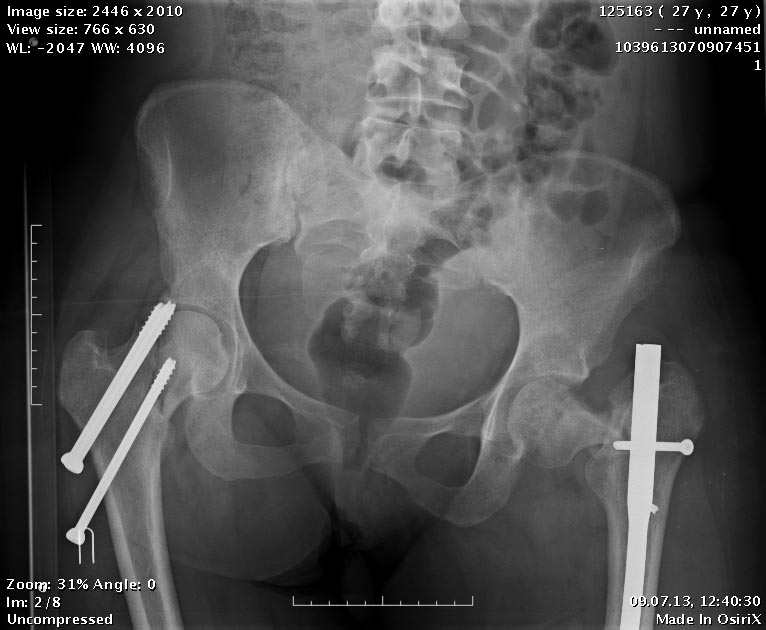

Продолжение истории, начало см. http://weborto.net/forum/1370513039/.Сегодня сделали левое бедро. Сделана аналогичная чрескожная вальгизирующая остеотомия, закрытый интрамедуллярный остеосинтез Affixus. Длинным, с учетом еще и бывшего диафизарного перелома. Были какие-то мысли насчет пластики дефекта шейки - решили воздержаться.